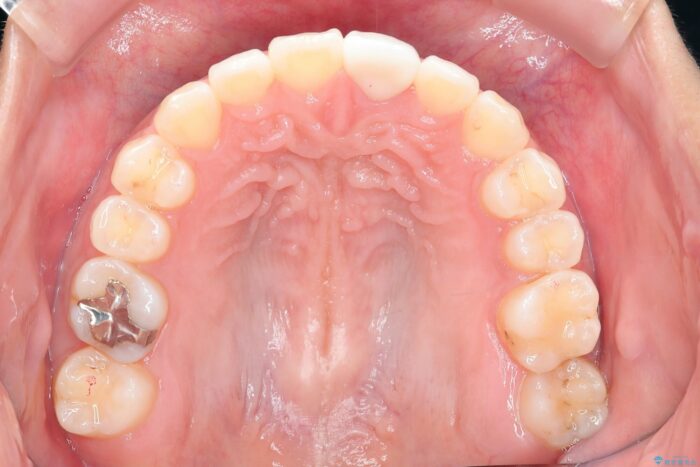

治療後について

1年で歯並び、嚙み合わせともにしっかりと改善されました。